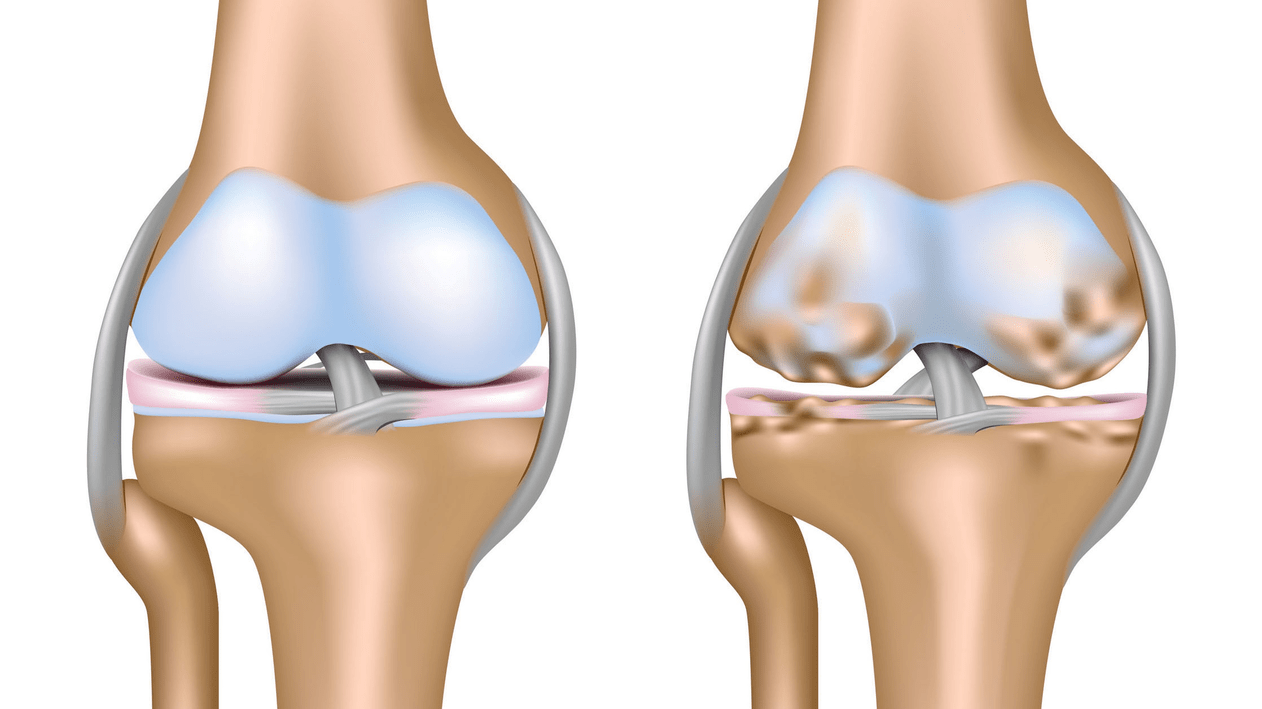

Arthrosis of the knee joint (gonarthrosis)is a progressive chronic disease of the knee joints with damage, thinning and destruction of its cartilaginous part (articular surfaces of the femur and tibia), as well as damage to the subchondral bone.It has been proven by studies (arthroscopy and MRI) that in addition to damage to the articular cartilage, the menisci and synovial membrane are involved in the process.Gonarthrosis is one of the most common orthopedic pathologies.There are its synonyms - osteoarthritis (OA), deforming arthrosis.The disease is an important socio-economic problem, as it is widespread and significantly worsens the quality of life of patients due to constant pain and, in addition, becomes a cause of high disability.

Until the mid-eighties of the last century, there was no unified definition of the disease.It was not until 1995 that the osteoarthritis committee of the American College of Rheumatology characterized the disease as the result of mechanical and biological factors leading to an imbalance between the processes of degradation and synthesis of the extracellular matrix of articular cartilage.As a result, fiber disintegration and degeneration occur, cracks, osteosclerosis and compaction of the cortical layer of the subchondral bone are formed, osteophytes grow and subchondral cysts are formed.

With arthrosis (osteoarthrosis), in addition to the progressive destruction of cartilage, loss of its elasticity and shock-absorbing properties, bones are gradually involved in the process.Under load, sharp edges (exostoses) appear, which are mistakenly considered “salt deposits” - with classic arthrosis, no salt deposition occurs.As arthrosis progresses, it continues to “eat” the cartilage.Then the bone becomes deformed, cysts form there, all structures of the joint are affected, and the leg becomes bent.

The first stage of the disease is characterized by primary changes in hyaline cartilage.Bone structures are not affected.The blood supply in intraosseous vessels and capillaries is disrupted.The surface of the cartilage becomes dry and it loses its smoothness.If the disease is accompanied by constant tense synovitis, then a Baker's cyst develops (hernial protrusion of the joint capsule of the popliteal region).After significant stress on the joint, dull pain occurs.There may be slight swelling that goes away after rest.There is no deformation.

Gonarthrosis, stage II

At the second stage, the cartilage layer becomes sharply thinner, and in some places is completely absent.Osteophytes appear along the edges of the articular surfaces.The qualitative and quantitative characteristics of the synovial fluid of the joint change - it becomes thicker, more viscous, which leads to a deterioration in its nutritional and lubricating properties.The pain is more prolonged and intense, and a crunching sound often appears when moving.There is a slight or moderate restriction of movement and slight deformation of the joint.Taking analgesics helps relieve pain.

Gonarthrosis, stage III

Lack of cartilage in most affected areas, severe sclerosis (hardening) of the bone, many osteophytes and a sharp narrowing or absence of the joint space.The pain is almost constant, gait is impaired.Mobility is sharply limited, and joint deformation is noticeable.NSAIDs, physiotherapy and other standard methods of treating knee arthrosis are ineffective.